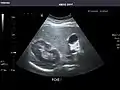

Left kidney

Kidneys: Right and left kidneys measure 11.5 cm and 12 cm in length respectively. No hydronephrosis. Small left lower pole kidney cyst.